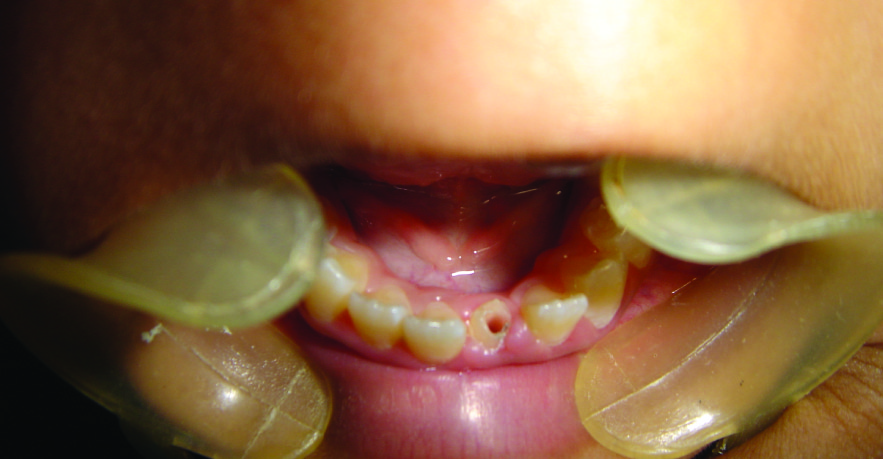

A 12-year-old female patient visited the Department of Pediatric Dentistry with a complain of broken left lower front tooth since four months. The patient did not complain of any pain [Table/Fig-1]. The parent of the patient told that the girl had a fall two years back in which the lower front tooth got broken. There was pain and tenderness reported at that time and they had visited a dentist for the same. On further enquiry it was revealed that the mentioned tooth had been root canal treated six months back and restored but the restoration came out within a month. The re-restoration also did not last more than 15 days. On examination lower left central incisor was fractured and there was neither pain reported nor tenderness to percussion. The tooth structure was less for a composite make-up or a crown. After thorough examination it was decided to go for a post and core and composite make up. As it was an anterior tooth in a young patient it was decided to go for fibre-reinforced composite (Ribbond, Ribbond THM, Ribbond inc.Seattle,WA) as post and core material as it is esthetic and has adequate strength. As the tooth was adequately obturated [Table/Fig-2], preparation of the canal space was done [Table/Fig-3,4]. The use of ribbond does not require additional tooth preparation as is required for metal posts. The remaining tooth structure being less, rubber dam isolation could not be accomplished and we decided for high suction evacuation with cotton rolls to be suitable for isolation. Gutta percha was removed using gutta percha solvent until the desired length for post was achieved. The post hole was shaped using Gates Glidden drills (Roydent, West Palm Beach, FL), cleaned with 5% sodium hypochlorite and dried. The width of Ribbond is to be decided on the root canal space available. The depth of the post space was measured using a periodontal probe, and a 3-mm-wide Ribbond was cut using special scissors provided with the kit (Ribbond starter kit, Ribbond THM, Seattle), measuring twice the depth of the post space and 3–4 times the height of the core build-up [Table/Fig-5] and placed in dual cure adhesive resin and set aside in light protected container. The root canal wall was etched, washed thoroughly and then air-dried gently. Excess water was removed from the post space using paper points . The dual cure adhesive resin (Ed Primer II A&B) was applied using a microbrush and gently air-dried to evaporate the solvent. Dual cure resin cement was then placed inside the canal space. The Ribbond was removed from the resin and the excess resin was removed using a hand instrument [Table/Fig-6], folded in a V-shape and coated with dual-curing resin cement (Panavia, Kuraray Medical Inc., Japan). The piece of ribbond was then placed in the post space in a labial-lingual direction with a periodontal probe [Table/Fig-7]. Excess resin cement was removed, and the cement was cured for 20 s. The two protruding ends of the Ribbond strips formed the reinforcement for the core build up to replace the lost coronal portion of the tooth. The remaining resin mix from the syringe was extruded onto this framework to create a core resembling almost like the shape of a lower central incisor. The space between the protruding ribbon ends was filled with resin so as not to leave any voids. Composite resin was also placed so as to cover the ribbon ends completely and leave none of them exposed on the outer surface of the core. All the material was thoroughly light cured to create a set surface. The material was left in the mouth for a couple of hours to ensure complete set of the self curing component of the resin mix. The result of this procedure came out to be a single piece post and core, which was bonded onto the root, creating a solid structure without any wedging effect on the root. Moreover, the resin conforming to the inside shape of the canal space ensured no voids and eliminated “fitting” problems normally associated with cast posts. The bands of Ribbond reinforced the resin material and made it extremely strong and durable. Bonding of the entire material also created a single block of post and core, which is the essence sought for favourable occlusal force transmission and for resistance against debonding of the entire unit. The best thing was, there was no metal to mask with the crown since the base shade of the composite was a close enough match to the tooth and was translucent. These strips, although opaque, were white in colour and after being completely encased in the composite, were not visible. However, they did not contribute to the colour of the core in any adverse way. The restorative procedure was completed by building up the tooth using dual cure hybrid composite resin following technique of small progressive build up without any matrix [Table/Fig-8,9]. All these increments were fully light cured. Finishing and polishing procedures were performed using composite contouring and polishing discs. The patient was advised for a crown at a later stage after complete development of occlusion. The patient has been under follow up for two years now with six month follow up intervals and the restoration is still in good condition [Table/Fig-10,11]. As because the occlusion is not yet established we have decided to give crown on a later date.